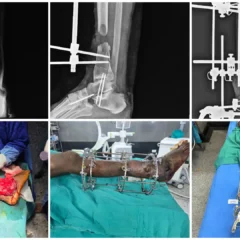

Right Trimalleolar Ankle Fracture Treated with ORIF and TBW Fixation | Balanku Hospital

Advanced Ankle Fracture Management at Balanku Hospital

Trimalleolar ankle fractures are complex injuries involving three components of the ankle joint — the lateral malleolus (fibula), medial malleolus, and posterior malleolus. These fractures often result from twisting injuries, falls, or road traffic accidents and require precise surgical management to restore ankle stability and prevent long-term complications.

At Balanku Hospital, we specialize in managing complex ankle fractures using advanced fixation techniques. We are pleased to share the successful treatment of Mr. Shivkumar, who presented with a right trimalleolar ankle fracture.

Surgical Procedures Performed

1️⃣ Open Reduction and Internal Fixation (ORIF)

Open reduction and internal fixation was performed for:

-

Fibula using plates and screws

-

Posterior malleolus using plates and screws

This ensured:

-

Accurate restoration of ankle alignment

-

Stable fixation of the lateral and posterior components

-

Proper joint congruity

2️⃣ Tension Band Wiring (TBW) for Medial Malleolus

The medial malleolus was stabilized using Tension Band Wiring (TBW) technique, which:

-

Converts tensile forces into compressive forces

-

Promotes stable bone healing

-

Provides strong fixation for small fracture fragments

The combined fixation approach restored full structural stability of the ankle joint.